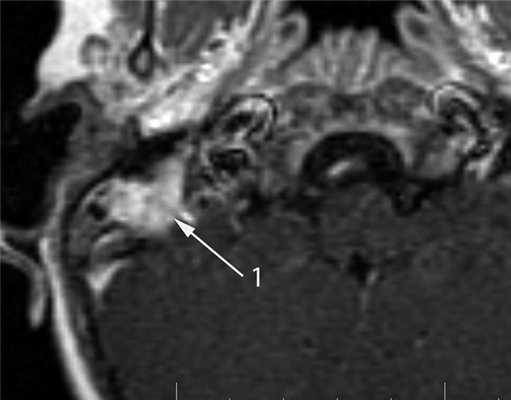

Недостатком КТ в диагностике опухолей среднего уха является низкая контрастность в изображении мягких тканей. В связи с этим существенную роль в диагностике опухолей среднего уха играет МРТ, которую используют для детальной оценки мягкотканных изменений. Эта методика позволяет выявить гетерогенный характер злокачественной опухоли, а также диагностировать распространение опухоли за пределы височной кости как экстра-, так и интракраниально. МР-характеристики злокачественных опухолей не являются специфичными: в Т1-изображении они имеют промежуточный сигнал, в Т2 — высокоинтенсивный сигнал, характерно значительное усиление сигнала после внутривенного введения контрастного агента [6, 7] (рис. 8). Рисунок 8. Лангергансоклеточный гистиоцитоз. МРТ в режиме Т1 после внутривенного контрастирования, коронарная проекция. В сосцевидном отростке определяется опухоль, активно накапливающая контрастный агент (1).